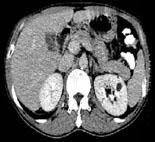

在下列几幅图片均为哪种疾病 ( )A、肾脓肿B、肾脂肪瘤C、肾错构瘤D、肾癌E、肾囊肿

问题 在下列几幅图片均为哪种疾病 ( )

选项 A、肾脓肿 B、肾脂肪瘤 C、肾错构瘤 D、肾癌 E、肾囊肿

答案 E